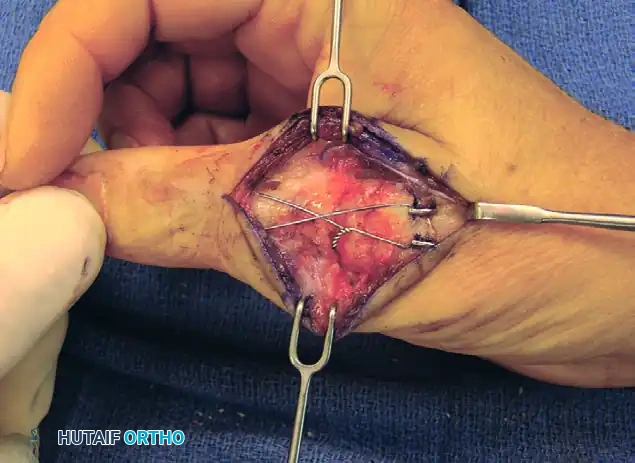

6. Tension Band Application and Compression

The application of the tension band wire is the critical step for achieving dynamic compression.

- Cross the two ends of the stainless steel wire over the dorsal aspect of the joint in a figure-of-eight pattern.

- Pass the wire ends around the protruding proximal ends of the longitudinal K-wires.

- Using heavy needle drivers or wire twisters, twist the wire ends together.

- Surgical Technique: Pull the wire radially outward while twisting to ensure the tension is distributed evenly and the wire tightens down firmly against the bone, compressing the arthrodesis site.

FIGURE 73-40F: Wire twisted and ends buried about the fusion site to achieve dynamic compression.